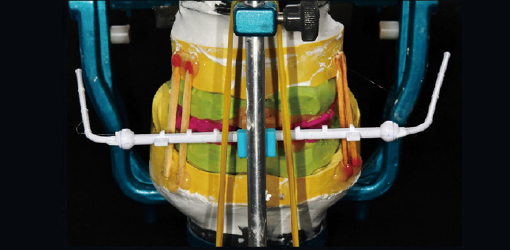

Apply JB Fork to maxilla with putty and VPS

Apply JB Fork to mandible with putty and VPS

Apply JB Fork to maxilla with putty and VPS

Apply JB Fork to mandible with putty and VPS

Apply JB Fork to upper and lower jaws

Apply JB Fork to upper and lower jaws